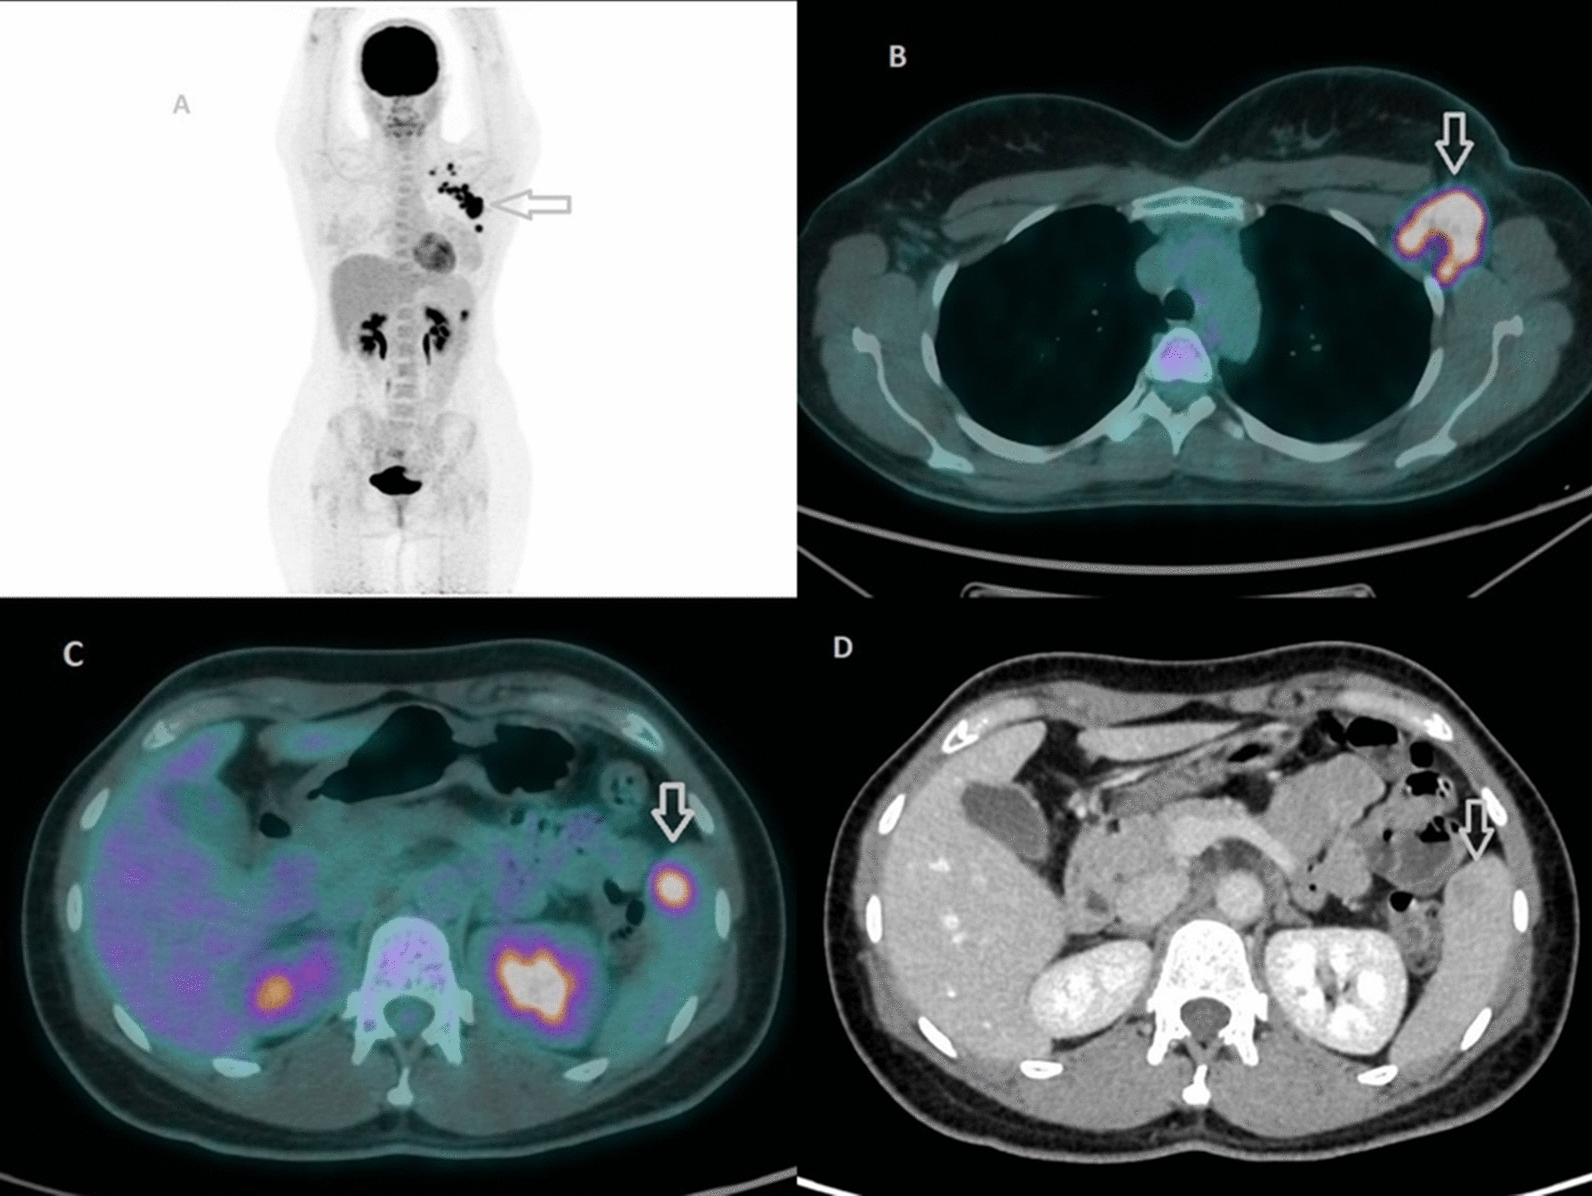

Our patient’s baseline staging PET/CT revealed an isolated hypermetabolic splenic lesion (SUVmax 6.5) with corresponding CT findings of a 16 mm hypodense nodule possessing a central low-density core and peripheral rim enhancement—features that are often worrisome for metastasis. Given the uncommon nature of splenic metastases in breast cancer, we pursued multimodal imaging. MRI characterization demonstrated no diffusion restriction and progressive contrast filling on delayed sequences, radiologically favoring an atypical hemangioma. Indeed, focal [18F]FDG uptake in atypical hemangiomas has been documented in both vertebral and hepatic locations, further complicating interpretation [16, 17]. In these reports, benign vascular tumors displayed intense [18F]FDG avidity akin to malignant lesions, likely reflecting the high endothelial cell turnover or inflammatory milieu within the lesion. What made our case particularly challenging was the combination of intense [18F]FDG uptake with CT features mimicking metastatic disease—a presentation that even experienced observers found disconcerting.

The therapeutic course provided an opportunity to further clarify the lesion’s nature. Following the first six cycles of neoadjuvant carboplatin, docetaxel, pertuzumab, and trastuzumab, repeat PET/CT demonstrated complete metabolic resolution of the splenic focus alongside reduction of the nodule to 5 mm on CT and preserved benign imaging characteristics on MRI. Such volume reduction of benign splenic lesions post‐therapy has been sporadically noted in the literature: one case series reported shrinkage of a splenic hemangioma following systemic chemotherapy for lymphoma [18]. However, to our knowledge, this is the first documented case of an atypical hemangioma in the spleen of a breast cancer patient evaluated in a true multimodal fashion—PET, CT, and MRI—both before and after neoadjuvant chemotherapy, with a demonstrated complete metabolic response.